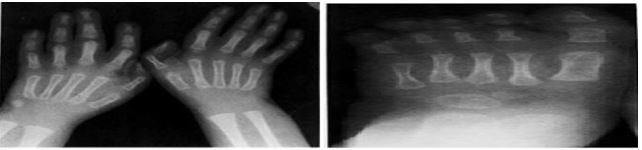

RADIOLOGIC FINDING : Roentgen graphic studies demonstrated identical abnormalities in each child . There was moderated to severbrachycephaly without evidence of premature fusion of cranial sutures . This was associated in each case with roentgenogramphic hypertelorism , an unusual number of Wormian bones increased calvarial vascular pattern and a borderline shorted mandible [13] . Skeletal maturation was below average but within normal limits for each child. Each patient had mild hind foot varus deformity and L5-S1 spina bifida osculates [14].

At 12 months , the patient was referred for mental retardation , sbrachycephaly with micrognathia and telecanthus (fig 1) . Length was 77cm (3rd to10th centile). In addition he had syndactylies of the fingers and toes 2-4 .There were also extensive dermal ridge anomalies with bilateral simian crease . The other anomalies are compared to those of the patient of Scott et al [1971] In Table1 . Delayed skeletal maturation made us first assume the presence of hypothyroidism . The first TRH-test showed values consistent with latent hypothyroidism and treatment with thyroid hormone (10µg T3 and 40µg T4) was instituted [18].